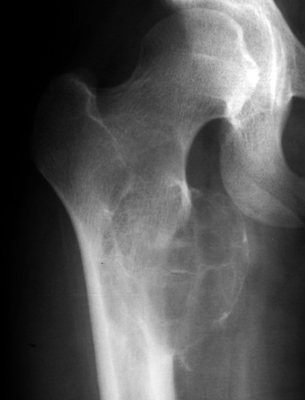

Frontal radiograph of the right hip and CT scan of the hips on a different patient. Both reveal a cystic bubbly lesion with fine internal septations. Additionally, compromise of the cortical margin of the lesion is present as well. The "blister of bone" sign refers to a bubbly cystic lesion with a saccular protrusion of the cortex with multiple fine internal septae. The shell of the lesion may fracture resulting in extravasation of blood into the adjacent tissues. This sign is highly characteristic of aneurysmal bone cyst.

AP hip - Click on the image for a larger versionA - Click on the image for a larger versionB